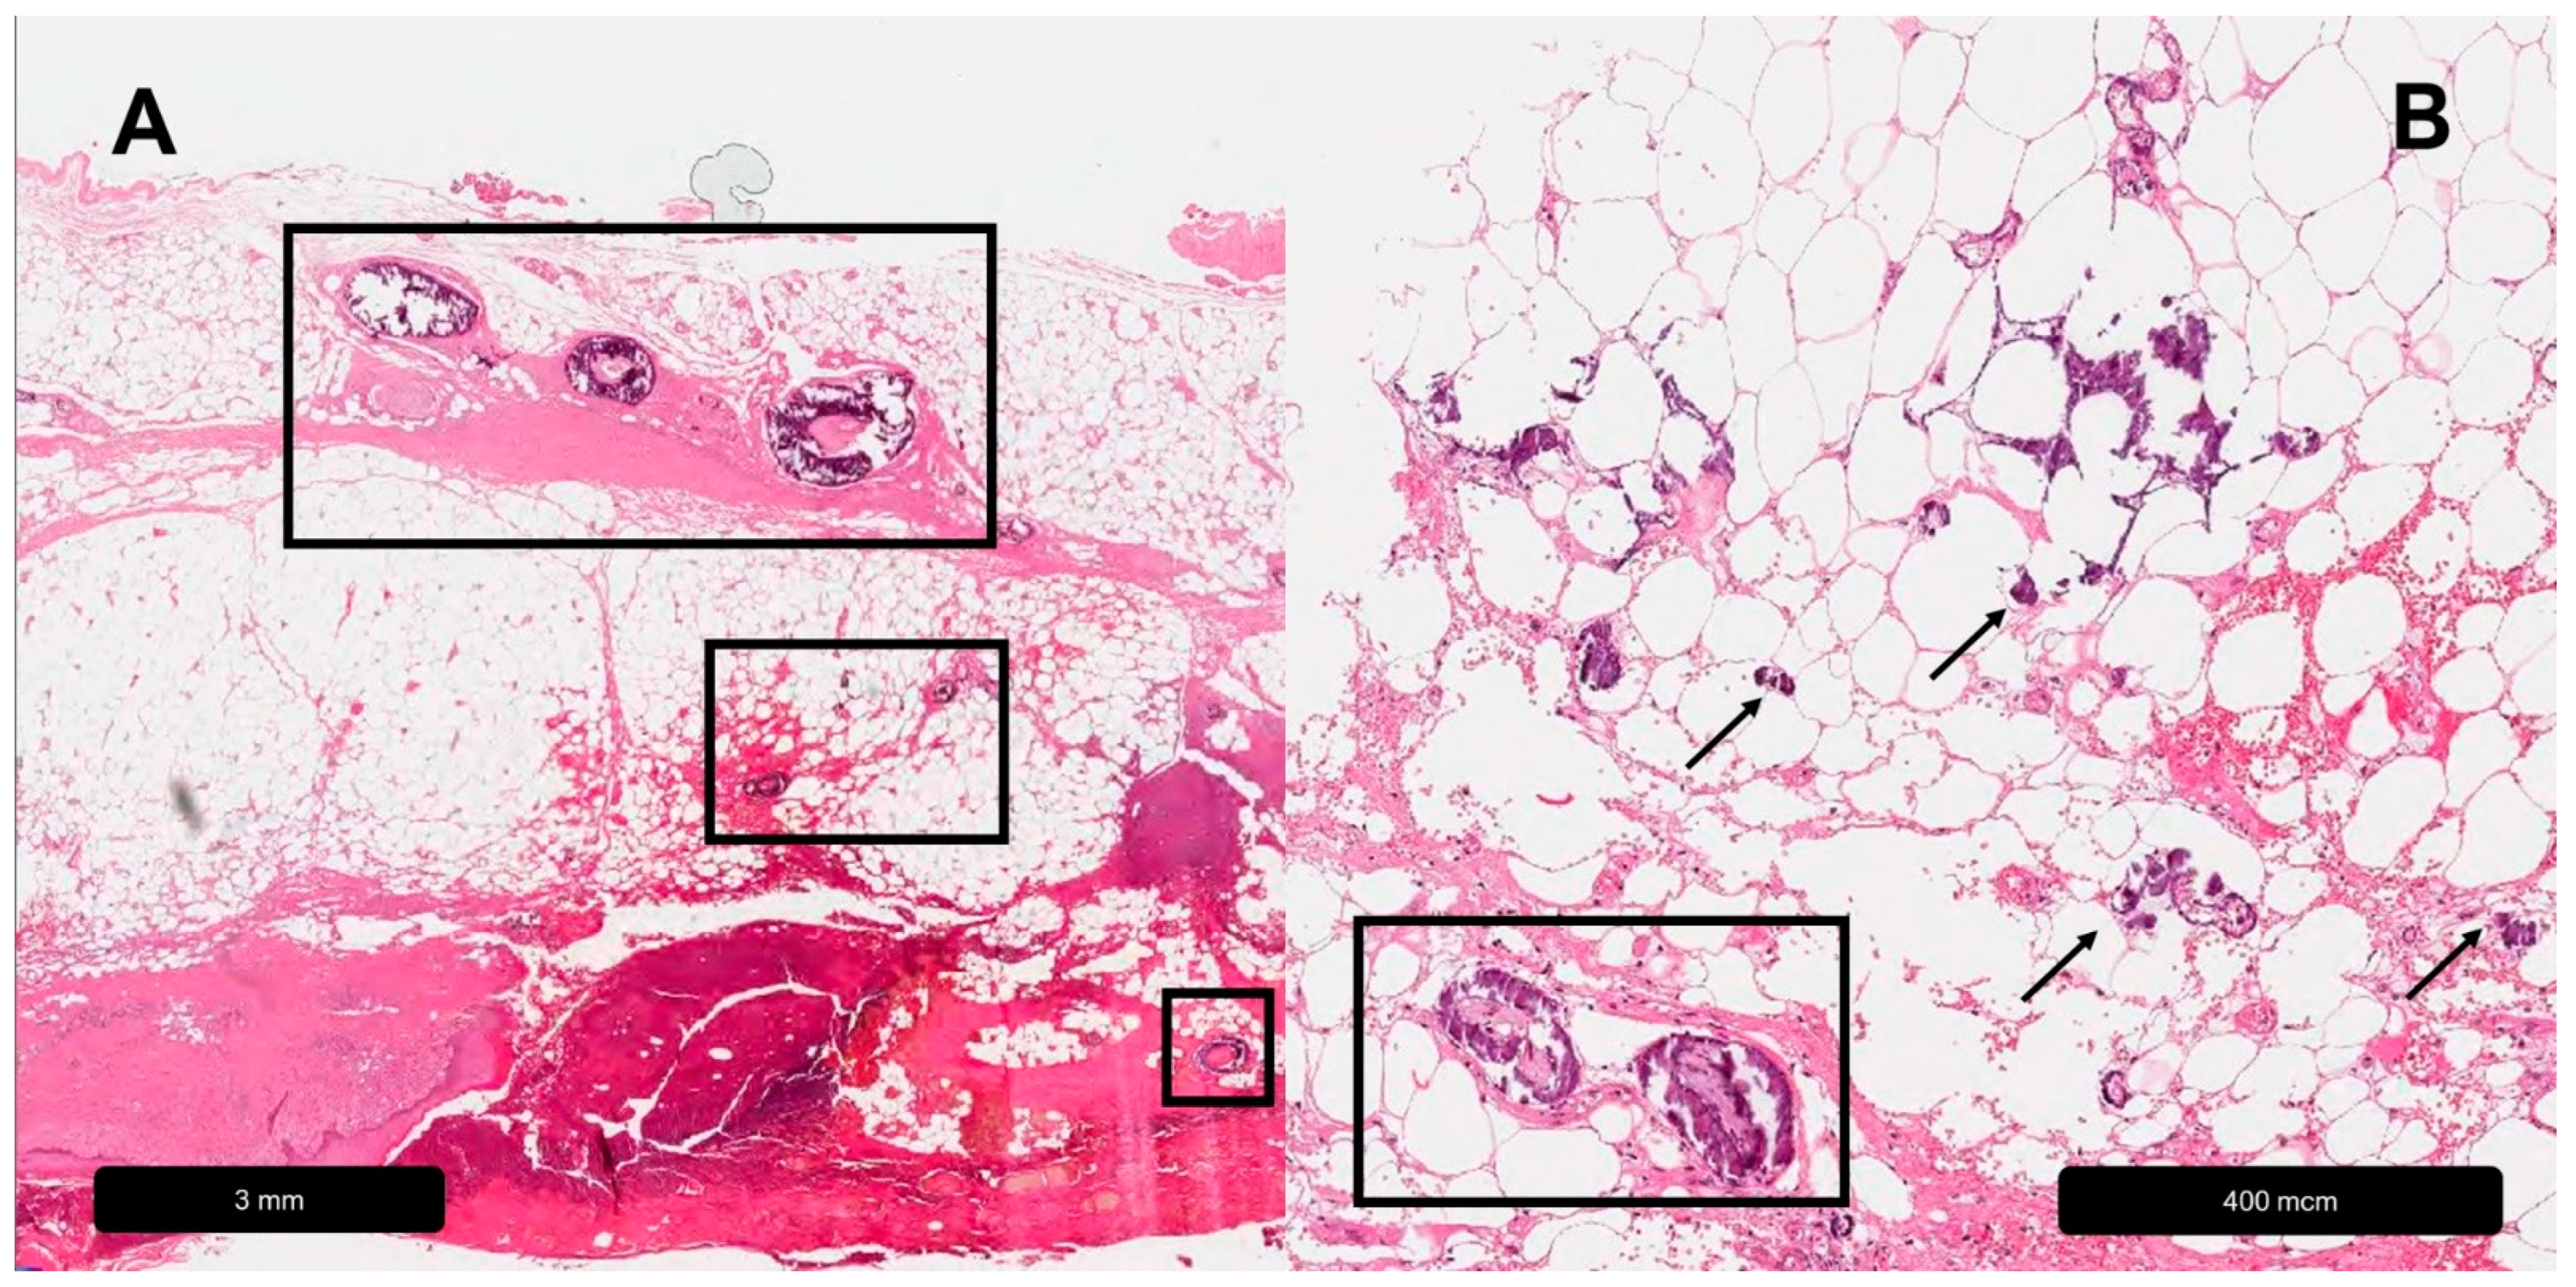

Figure 4.

Calciphylaxis. (A) Overview, black rectangles = calcifications in different layers of the skin. (B) Magnification, black rectangle = vessel-associated calcifications, black arrows = extra-arterial calcium deposits.